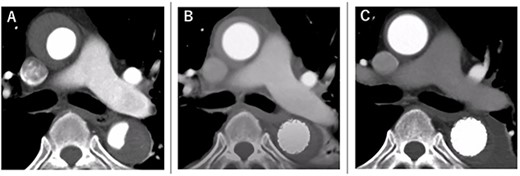

A 68-year-old man developed severe acute back pain and was diagnosed with acute type A aortic dissection with enhanced computed tomography (eCT) in the emergency department of our institute (Fig. 1A and B). The false lumen of the arch and ascending aorta was thrombosed (the maximum short diameter of the ascending aorta was 43.3 mm, the maximum diameter of the false lumen at the ascending aorta was 17.7 mm, Fig. 1C), and the primary entry was placed at the descending aorta. In addition, malperfusions were observed in the right renal artery and both iliac arteries (Fig. 1D). Therefore, we decided to perform TEVAR with the petticoat technique because of the rapid increase in true lumen blood flow.

eCT at diagnosis. (A): Sagittal view, (B) 3D reconstruction of the ascending and descending aorta, (C): Axial view of the ascending aorta and (D): 3D reconstruction of the abdominal aorta and iliac artery.

The course of aortic remodeling at the ascending aorta. (A): Preoperative, (B): 1-day postoperatively, (C): 11-day postoperatively (see Video 1).